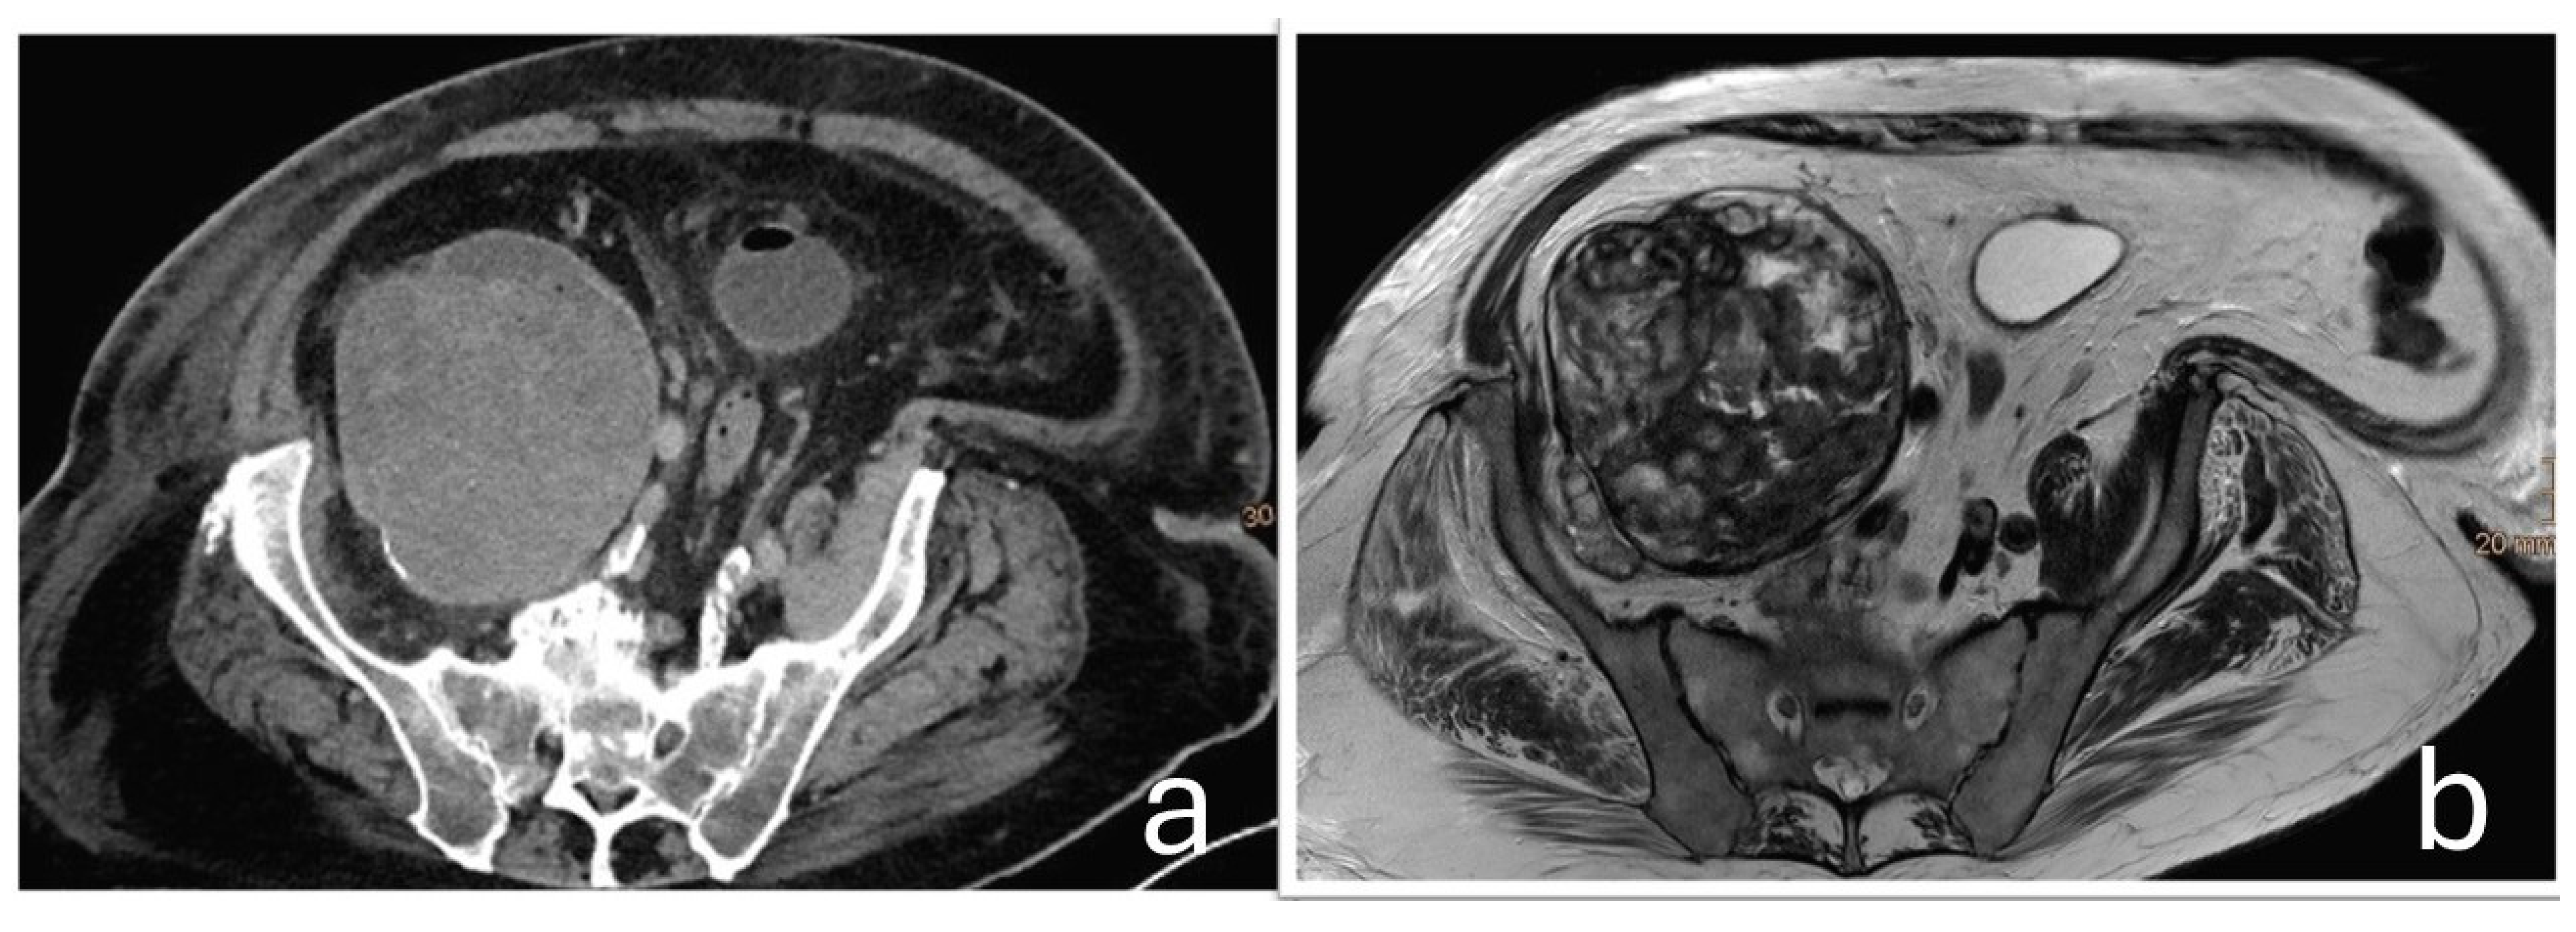

The tissue was macroscopically trimmed and representatively embedded in paraffin. Sections were stained with hematoxylin and eosin and examined by light microscopy. Histological analysis showed a mixed chronic and active inflammatory response with metal and polyethylene wear particles, necrosis, and hemorrhage. The surrounding fibrotic capsule exhibited a lymphohistiocytic and florid inflammation. Findings were consistent with an organizing, encapsulated hematoma, without evidence of neoplastic infiltrates (Figure 6).

Figure 6. (a) Hematoxylin and eosin (H&E) staining at 200× magnification. It demonstrates a mixed inflammatory response. Numerous neutrophilic granulocytes and areas of erythrocyte extravasation are visible. Macrophages are prominent, including hemosiderin-laden macrophages (identified by brown pigment, →) and macrophages containing metal debris (black pigment, ∆). Additionally, there is extensive capillary proliferation (*), indicative of a chronic inflammatory process. (b) H&E staining at 400× magnification. It reveals a granulomatous inflammatory reaction with increased numbers of macrophages, predominantly with an epithelioid phenotype (←), and so-called ‘ghost particles’ (○): Polyethylene appears optically empty in H&E staining and presents as narrow, spindle-shaped or roundish voids, often without coloration (as polyethylene is not stainable).